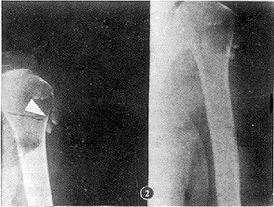

2.1 X线表现:患病关节间隙或关节周围如滑囊与腱鞘滑囊内见一枚或多枚游离体,大小不一,形态从绿豆大至长条形,甚至似“钟乳石”样(图1),部分呈椭圆形,最大3 cm×1.5 cm×1.5 cm(图2)。游离体钙化与骨化常不均匀或呈环状或呈点、斑点样改变,多位于游离体外围。游离体中心为一密度减低区。1例CT见游离体位于关节囊内呈沙粒样改变(图3)。除上述外,患病关节间隙变窄,关节骨面吸收,而致增生肥大3例(图4),关节囊肿胀4例,其余关节骨与关节间隙均正常。

图1 右膝关节髌上囊区域见一大骨化结节,手术证实从膑上囊以蒂与滑膜相连,另有二枚小骨化结节

图2 右肩关节三角肌滑囊区域见多个长条形形如“钟乳石”样钙化,手术证实位于三角肌滑囊内以蒂与滑膜相连,最大2.2cm×1.1 cm×1.2 cm,最小0.9 cm×0.4 cm×0.5 cm一共8枚